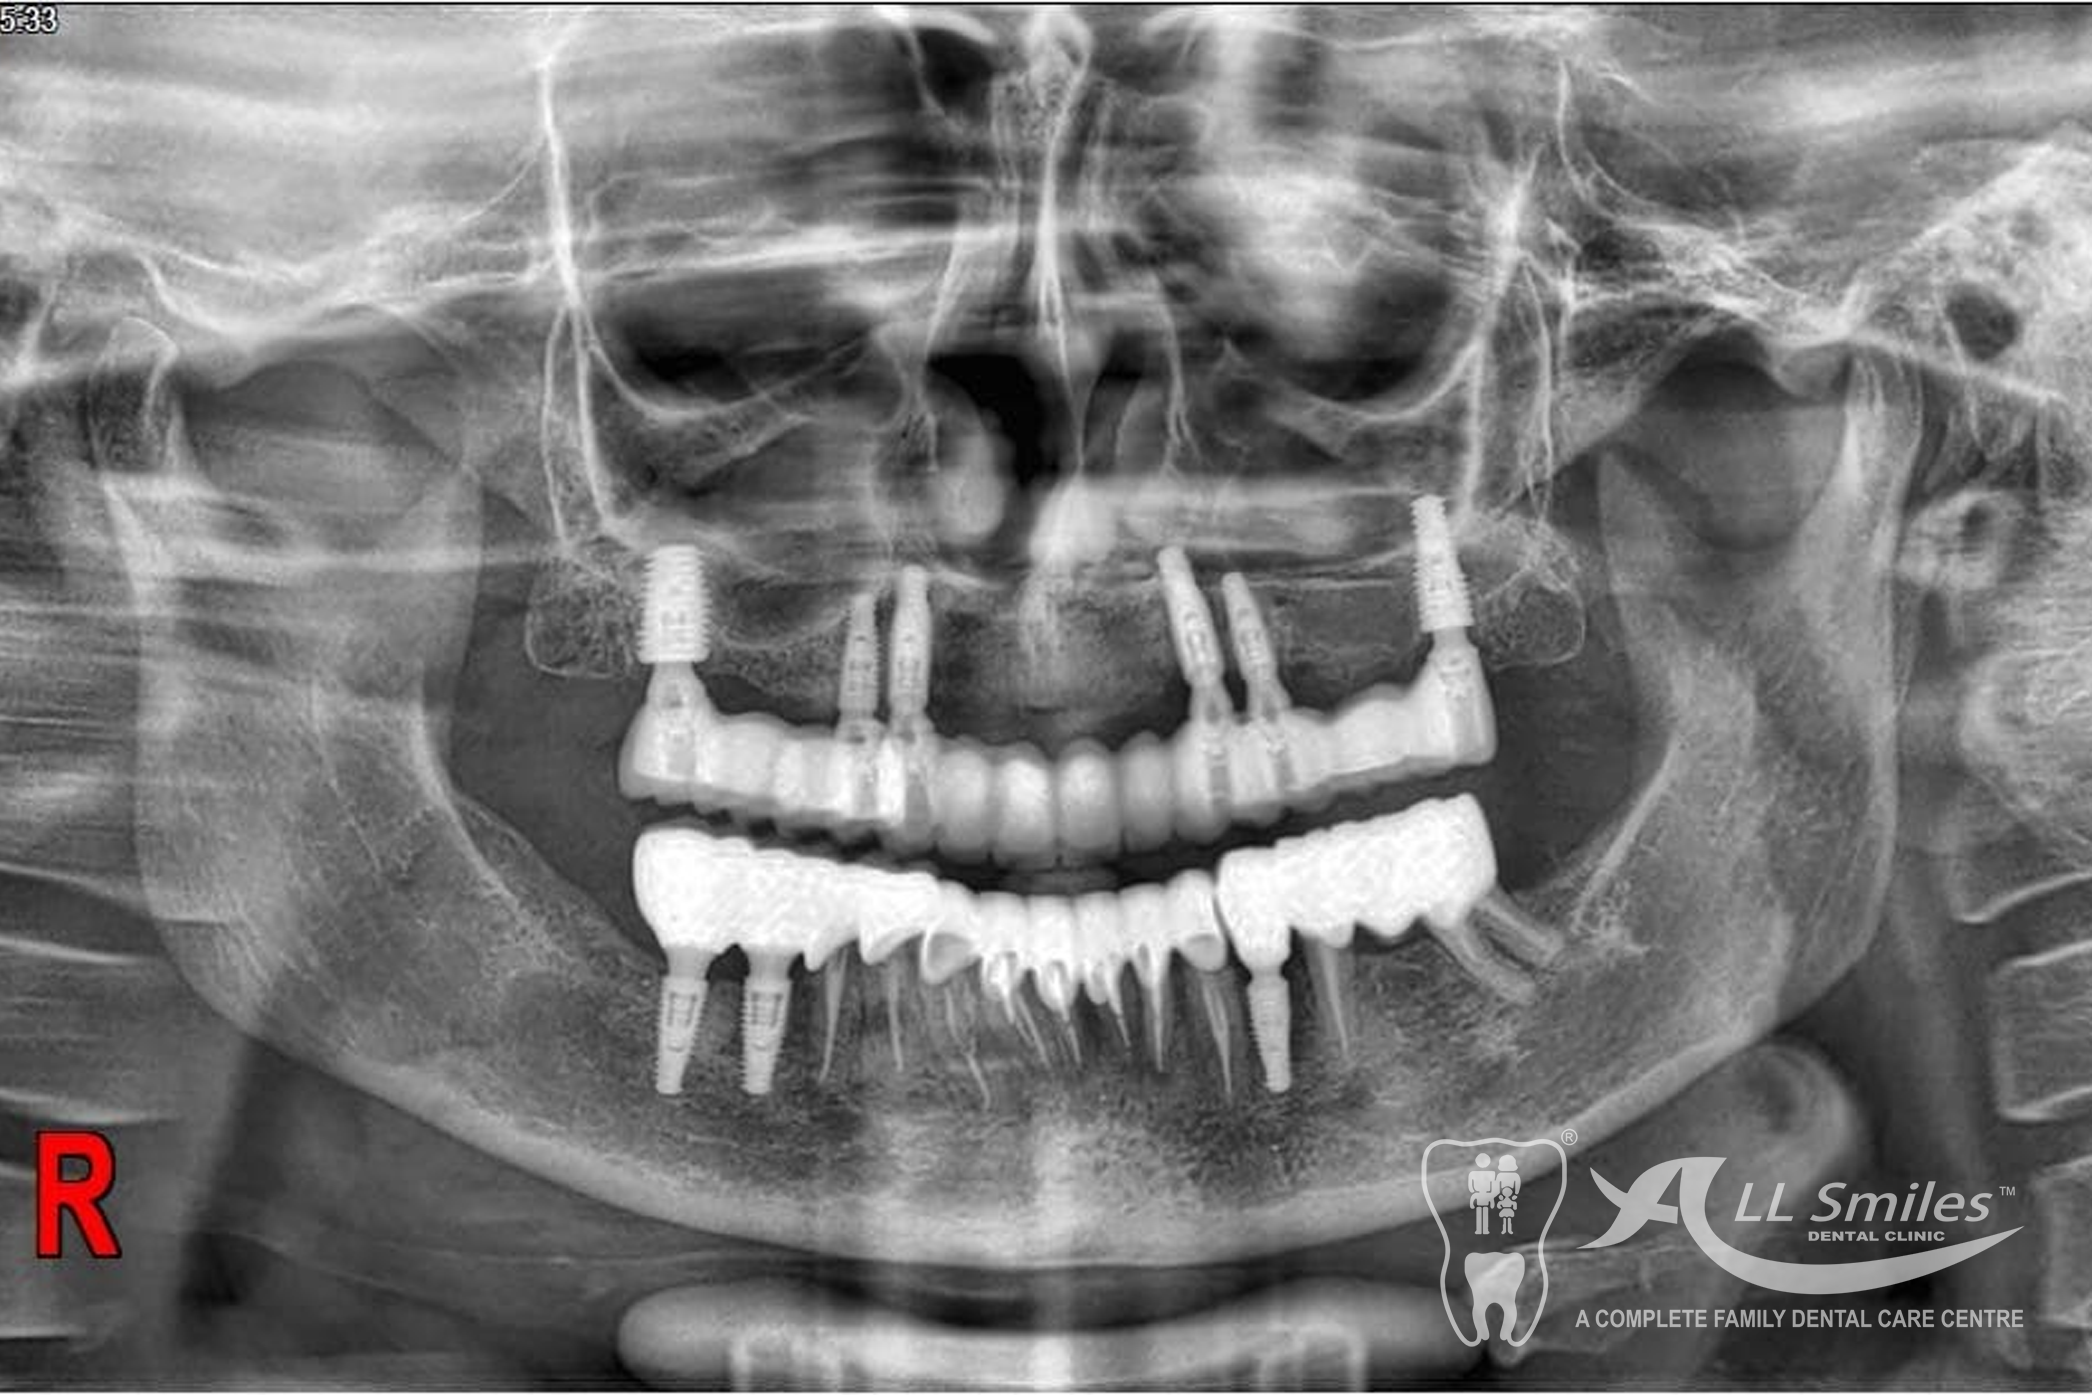

You will still be able to laugh with dental implants. As few as two to four new roots will be enough to provide a firm base for a full denture. A bridge can be fixed to six implants. This will give you a high degree of security in every situation because nothing can come loose unexpectedly. No more embarrassing surprises.

- All on 4 or All on 6: A bridge can be permanently anchored to 4 or 6 implants in your jaw. The Implants for each arch are placed in a single appointment. It is often possible to fix the provisional denture to the new roots at the same time implants are placed in the jaw. You come to the appointment in the practice and leave few hours later with firmly fixed, beautiful teeth. After the healing phase this is replaced by the permanent ceramic or acrylic prosthesis.

A bridge can be permanently anchored to 4 or 6 implants in your jaw. The Implants for each arch are placed in a single appointment. It is often possible to fix the provisional denture to the new roots at the same time implants are placed in the jaw. You come to the appointment in the practice and leave few hours later with firmly fixed, beautiful teeth. After the healing phase this is replaced by the permanent ceramic or acrylic prosthesis.